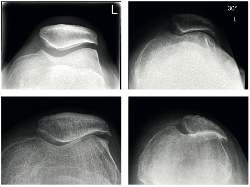

Bei ca. 5-10% der Arthrosepatienten ist Verschleiß des Kniegelenkes auf das Kniescheibengelenk konzentriert (Gelenkskammer hinter der Kniescheibe). Die beiden Hauptkammern des Kniegelenks sind noch gut erhalten. In dem Bemühen so viel Biologie zu erhalten wie möglich kann es bei jenen Patienten sinnvoll sein nur die Kniescheiben-Gelenkskammer zu ersetzen (Patellofemoralprothese).

Bei dieser Operationsart werden lediglich die Rückseite der Kniescheibe und die Kniescheibengleitrinne mit Implantaten ausgekleidet. Alle Bänder und die knöchernen Hauptanteile des Knies bleiben erhalten.